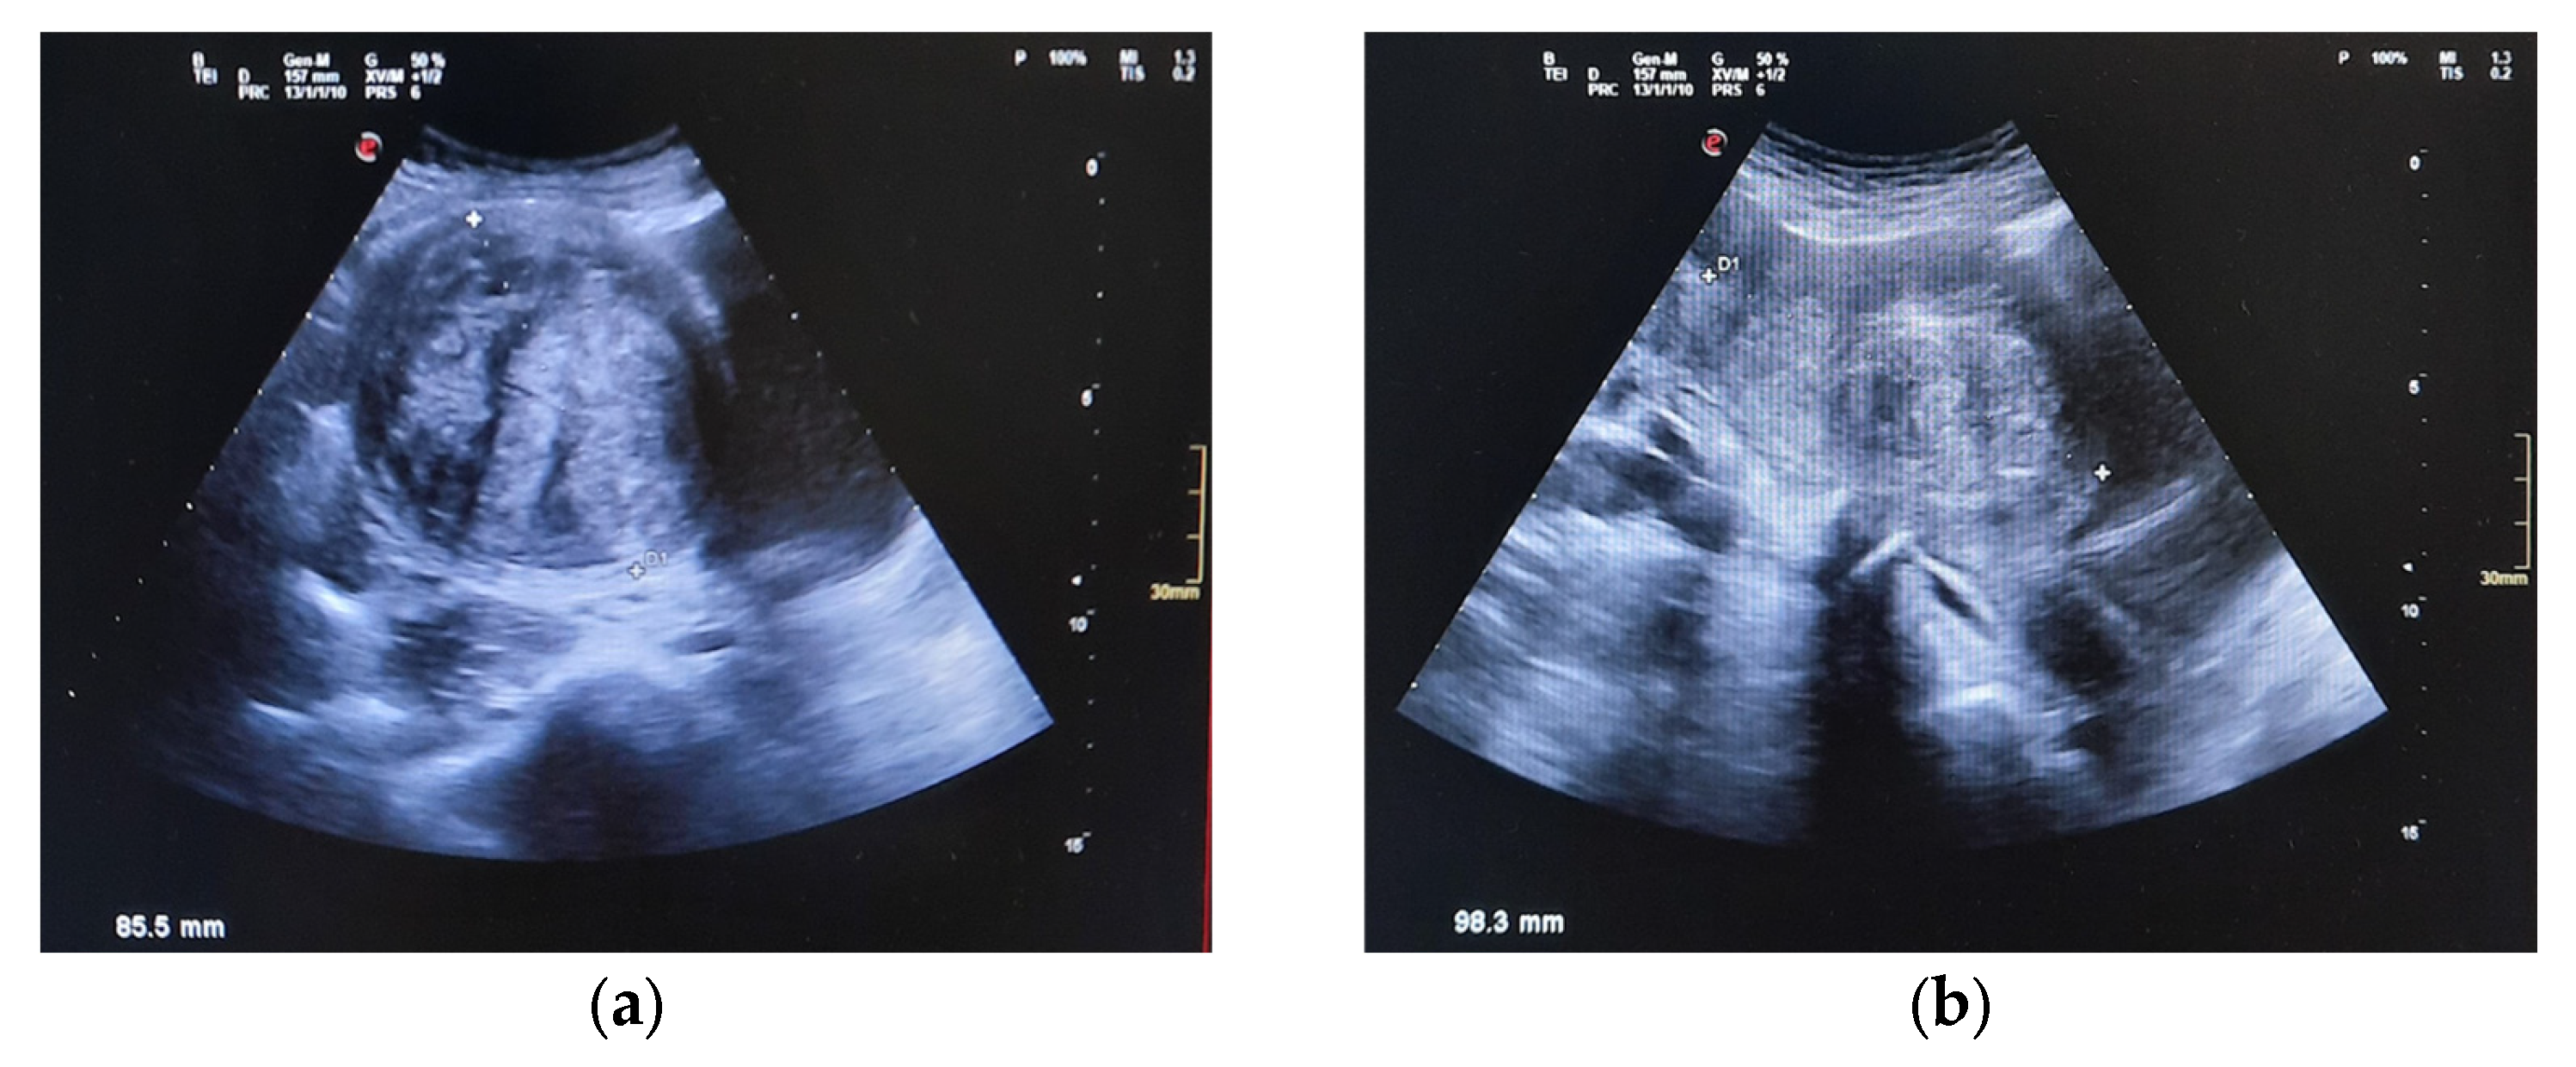

| 27 December 2024 | Abdominal US reveals 9 cm pelvic mass suggestive of fibroids; urgent gynecologic evaluation recommended. |

| 15 April 2025 | Pelvic MRI confirms multiple intramural and submucosal fibroids; significant uterine deformation. |